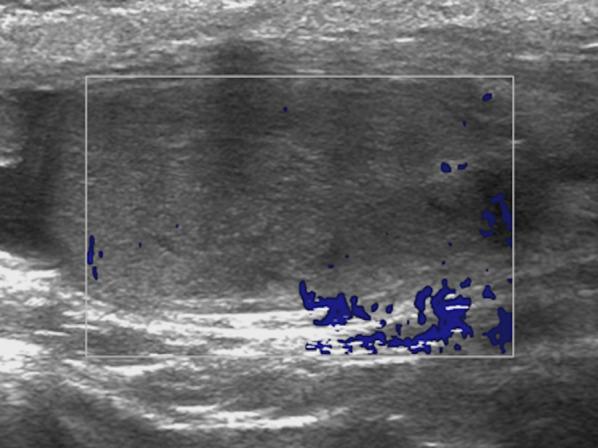

Identifying the deceiver: the non-neoplastic mimickers of genital system neoplasms.

Tumors of the genital system are common and imaging is of crucial importance for their detection and diagnosis. Several non-neoplastic diseases may mimic these tumors and differential diagnosis may be difficult in certain cases. Misdiagnosing non-neoplastic diseases as tumor may prompt unnecessary medical treatment or surgical interventions. In this article, we aimed to present the imaging characteristics of non-neoplastic diseases of the male and female genital systems that may mimic neoplastic processes. Increasing awareness of the imaging specialists to these entities may have a severe positive impact on the management of these patients.